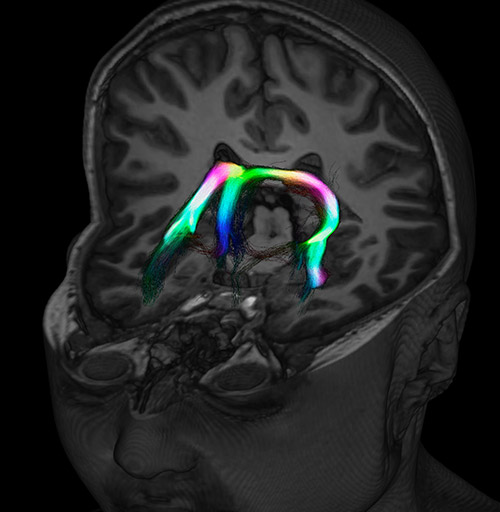

Fiber tracking based on CSD analysis of multishell DWI data and probabilistic tractography.

Fiber tracking from the left and right hippocampi to the fornix.

Fiber tracking from the left and right hippocampi to the fornix (green), and the corticospinal track based on a seed region of the posterior limb of the internal capsule.

DEC TDI

Super-resolution directionally encoded color track-density imaging overlaid on T1-weighted structural MRI.

Super-resolution directionally encoded color track-density imaging